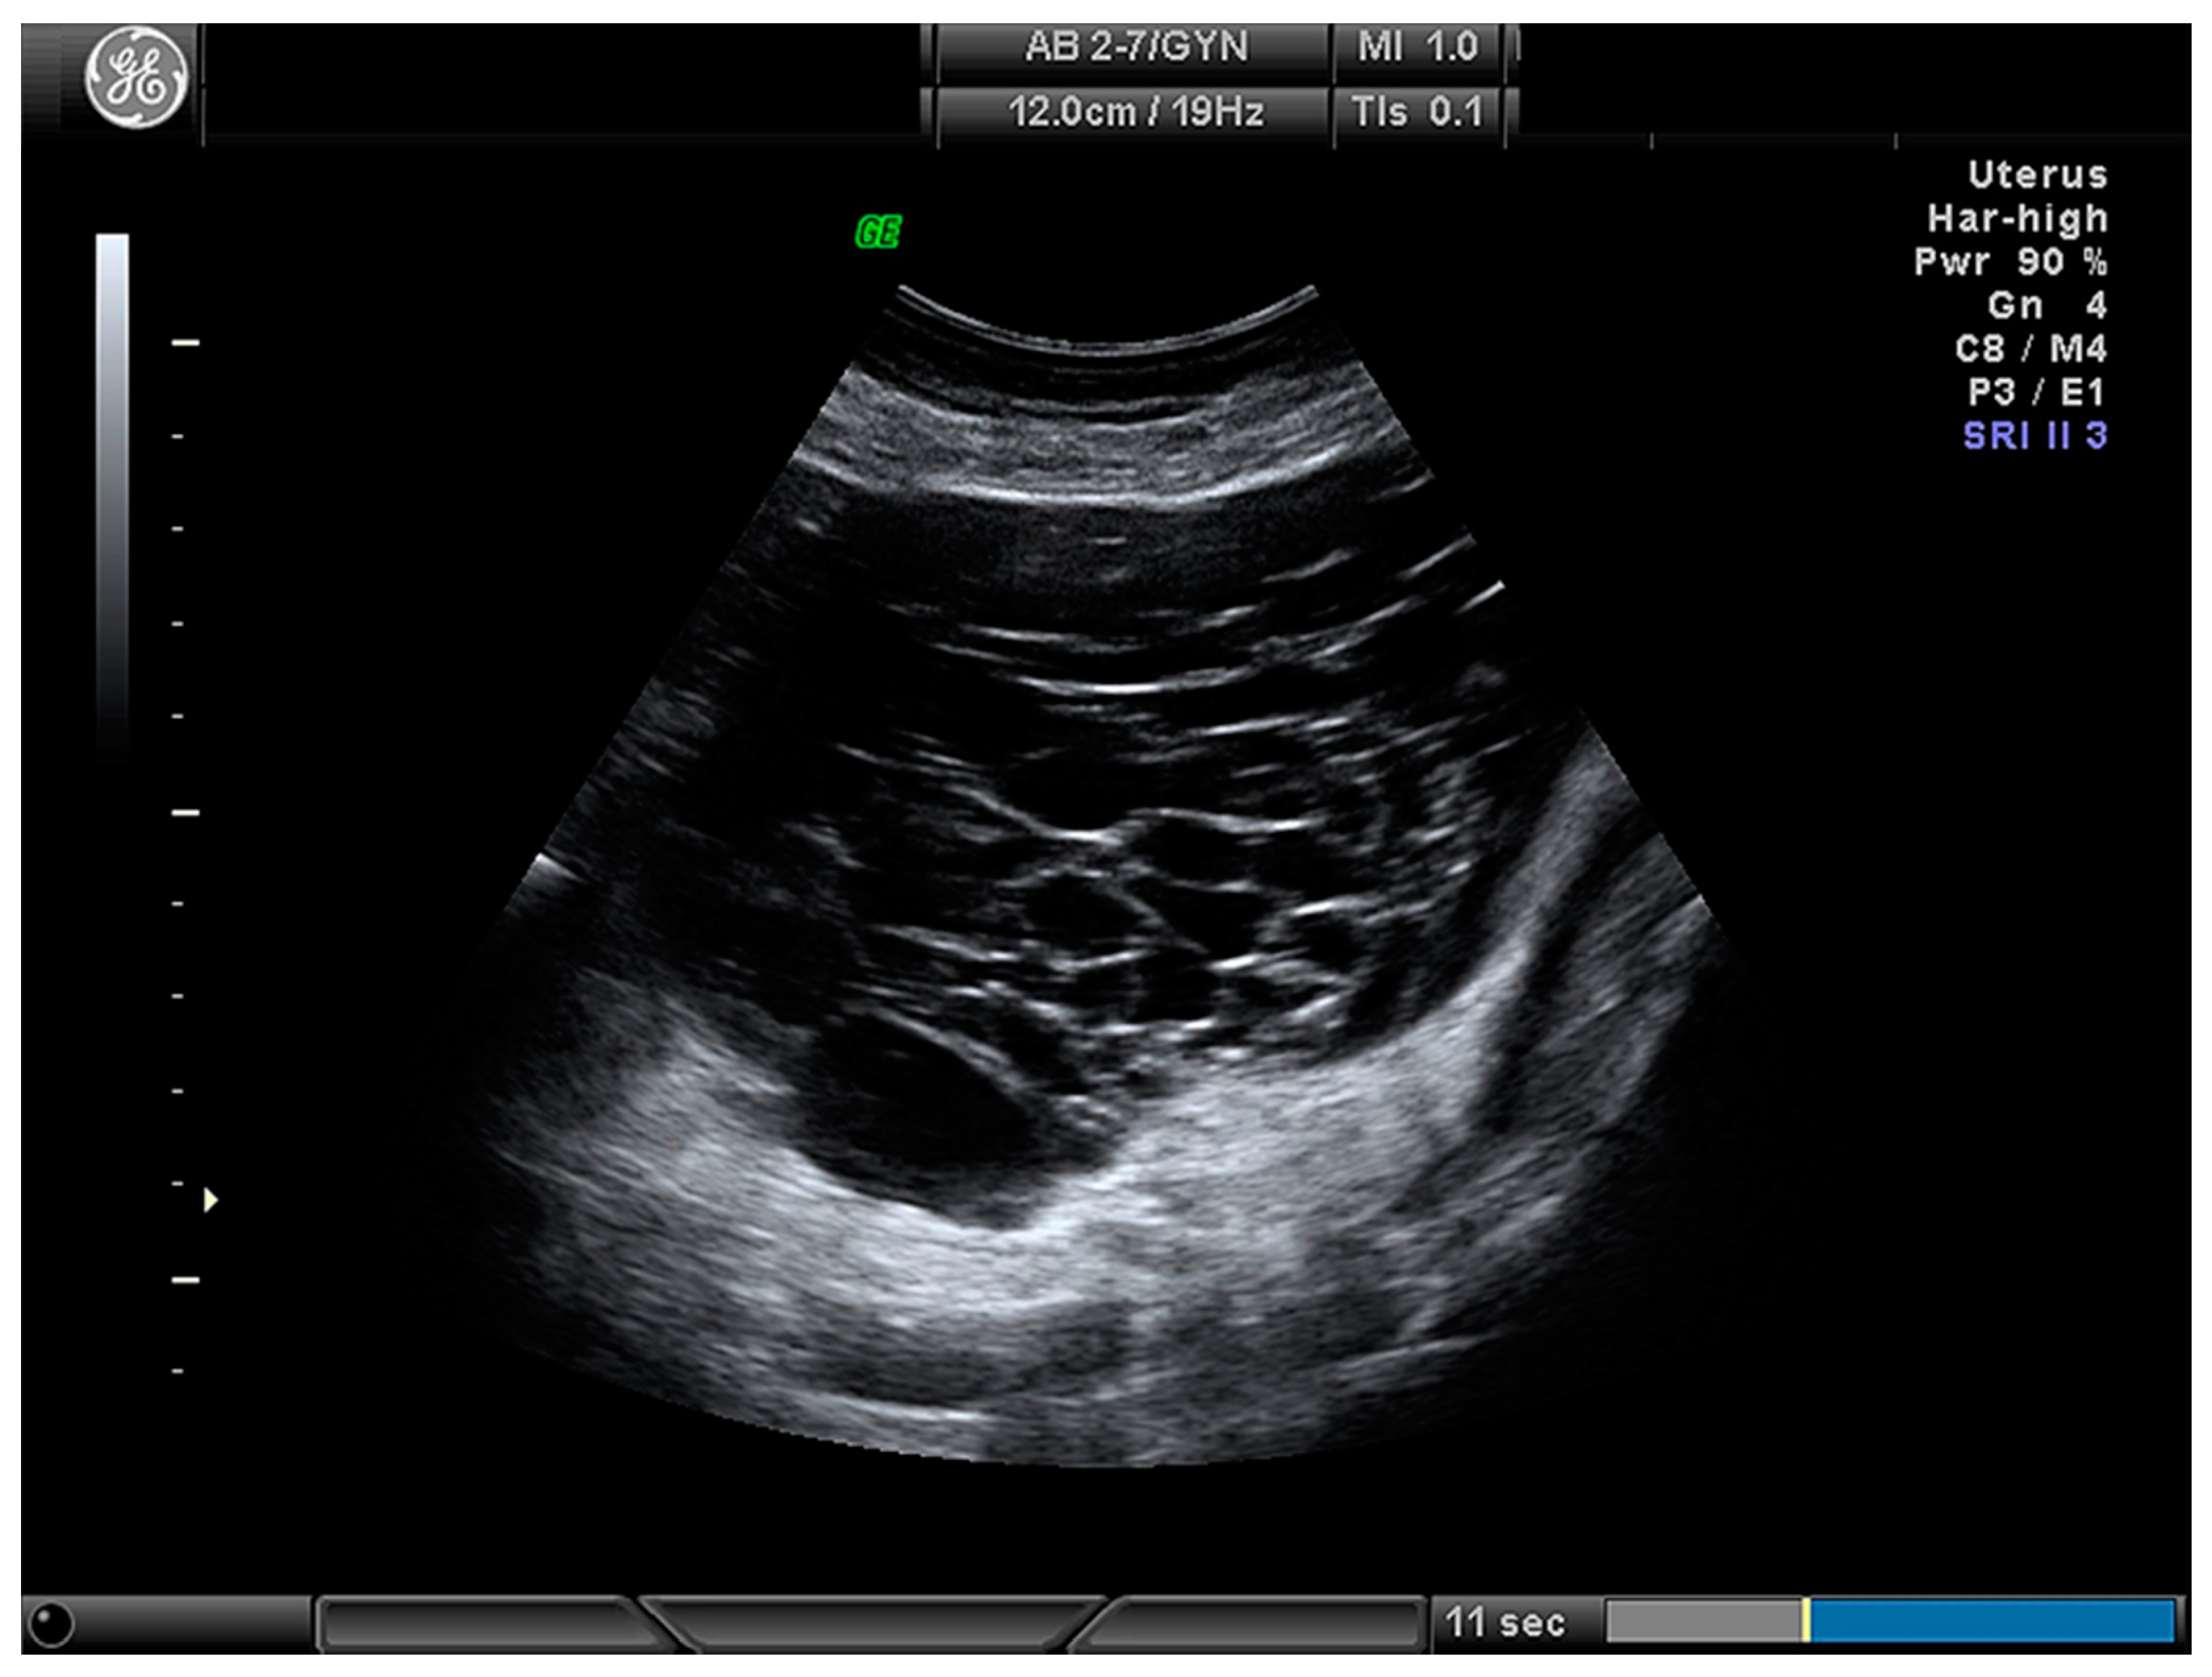

| Cystic (Figure 3) | 24 (28.2) |

| Cystic–solid (Figure 4) | 61 (71.8) |